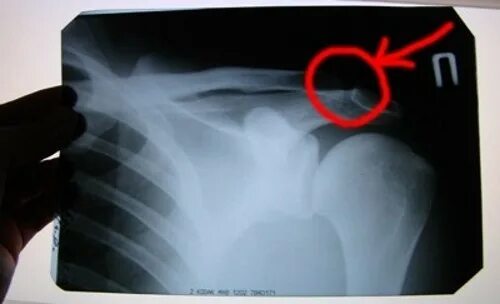

Частичный отрыв